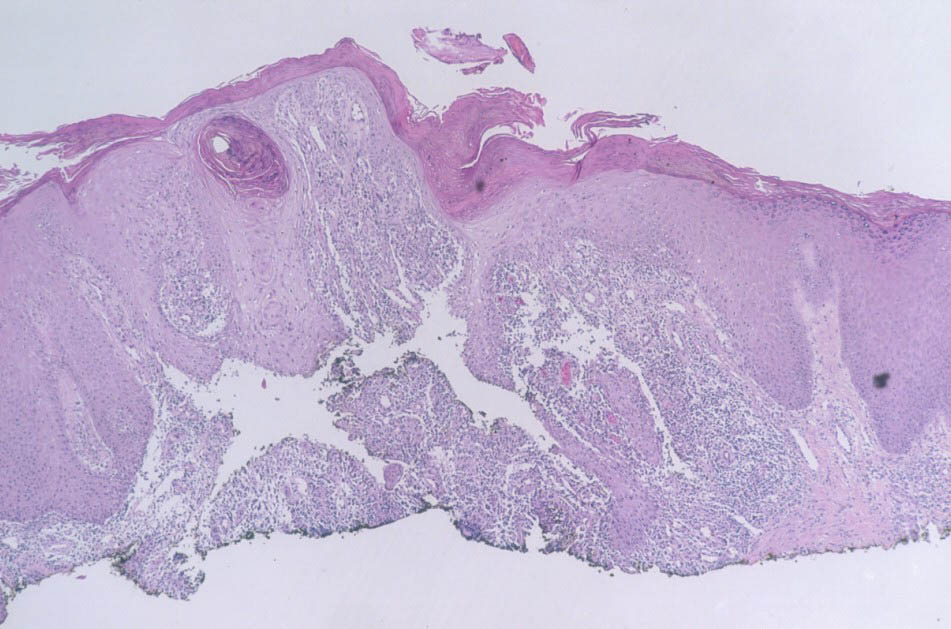

Histopathology.

Early lesions no more than 2 or 3 months old show a nonspecific inflammatory infiltrate composed of neutrophils, monocytes, and macrophages. In lesions about 4 months old, a few multinucleated giant cells and a few small epithelioid cell granulomas usually are present, and in lesions 6 months old or older, typical tubercles or tuberculoid structures may be seen (126). Areas of necrosis are only occasionally present in the centers of the granulomas. The epidermis often shows marked hyperkeratosis with an acute inflammatory infiltrate and ulceration .

Acid-fast bacilli usually can be identified in histologic sections of early lesions that show a nonspecific inflammatory infiltrate. In contrast, tuberculoid granulomas generally no longer show acid-fast organisms unless areas of central necrosis are present. Although primary lesions usually require a few months for the formation of tuberculoid granulomas, the sporotrichoid nodules that arise later show tuberculoid granulomas and a lack of acid­fast bacilli even when they have been present for only a few weeks.